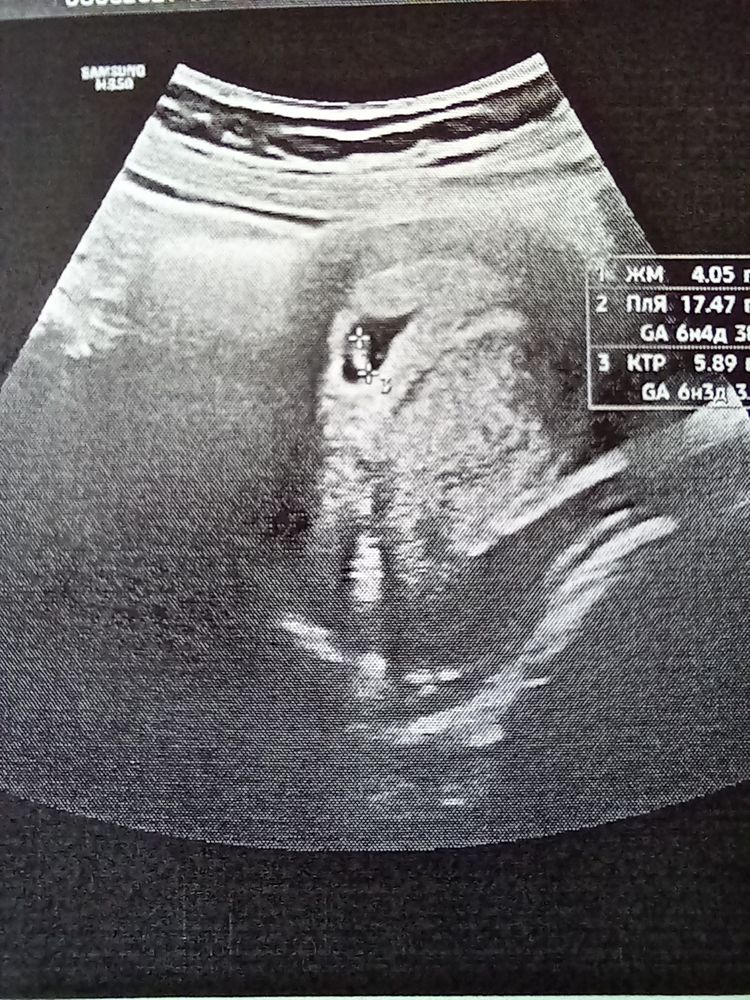

16дпп узи

Девочки,так как вчера была кровь,пошла я на узи на 16 день переноса,а не на 21 как планировала

ПЯ в матке,Желточный мешочек есть

но плодное яйцо с неровными краями,врач сказала не знает почему так,надо смотреть как,что дальше будет